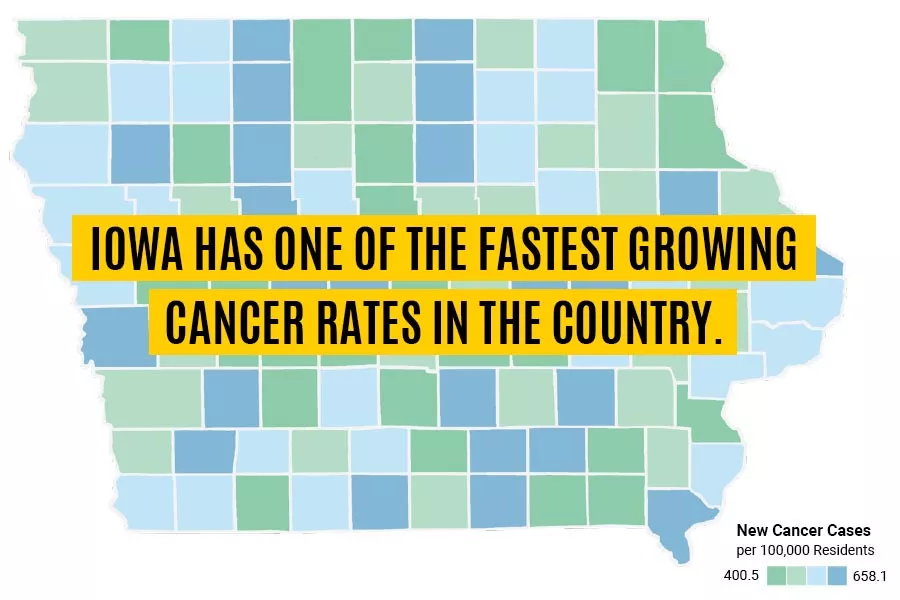

Foaming in on cancer

Taking inspiration from the culinary arts, Iowa researchers are exploring gas-entrapping materials to boost chemotherapy and radiation treatments.

Featured Headlines

October 7th, 2024 - University of Iowa Health Care and Mission Cancer + Blood today announced an agreement to create a comprehensive cancer care network uniquely positioned to tackle Iowa’s elevated cancer rates.